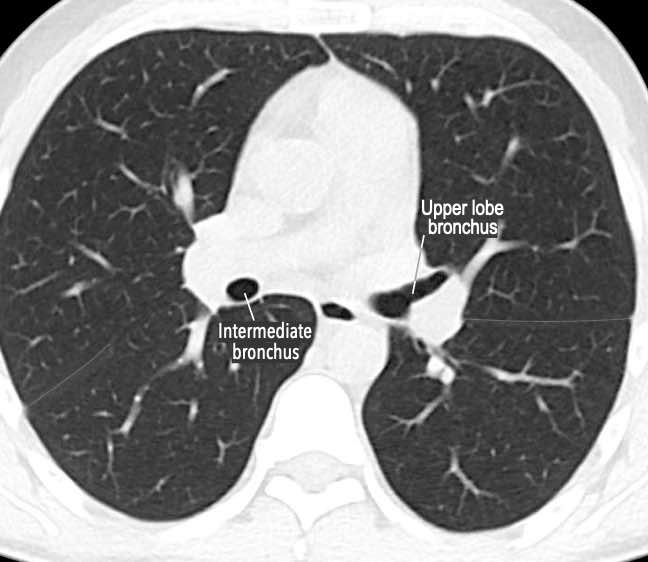

Phế quản trên CT

Cuộn qua các hình ảnh để quan sát khí quản phân chia thành phế quản chính phải và trái, sau đó tiếp tục phân chia thành các phế quản thùy và phế quản phân thùy.